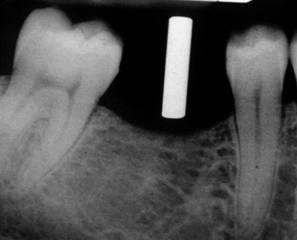

PLACEMENT OF DENTAL IMPALNT

1 ST PREMOLAR EXTRACTION

BONE GRAFTING

4 MONTH HEALING

PLACEMENT OF IMPLANT

PILOT DRILL

IMPLANT IN SITU